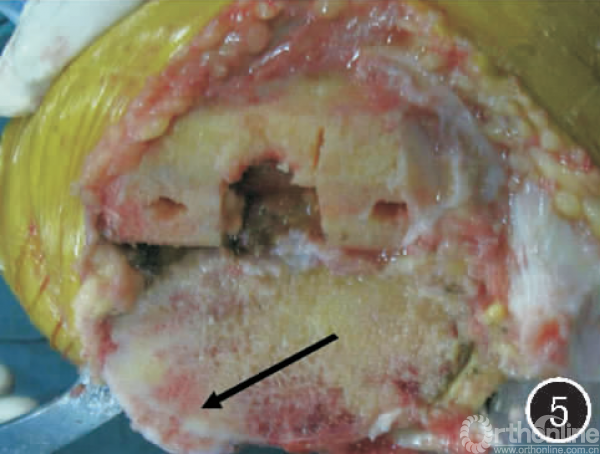

图5屈膝、内翻畸形患者胫骨平台截骨后,见骨赘与正常骨质之间一隐约的白线(箭),为尚未骨化的软骨组织

当患者高度屈膝、内翻畸形后,对应的股骨和胫骨也会发生旋转改变,胫骨平台的内、前方会产生大量的骨赘,其目的是要维持膝关节的稳定。Brander等[5]也认为骨赘的形成与维持膝关节的稳定性有关。虽然这些骨赘与胫骨平台骨质连成一体,但我们经常会看到,这些骨赘与正常骨质之间会有一条隐约的白线,切骨后这些骨赘像草帽的边缘一样与胫骨相连(见图3-5)。

因此,正确的做法是胫骨平台假体必须要放置在白线之内,否则就要旋转错位。如果我们不将胫骨平台假体放置在白线之内,那就会使胫骨平台假体旋前,进而造成股骨与胫骨的受力点向胫骨平台后方转移,产生胫骨平台后方的应力集中,长期应力集中而造成胫骨平台聚乙烯垫的磨损和破坏。正确的手术操作应该是:把胫骨平台假体放到白线内之后,切除假体没有覆盖的骨赘,这样既矫正了旋转畸形,又能松解膝关节内侧副韧带的紧张(见图6)。